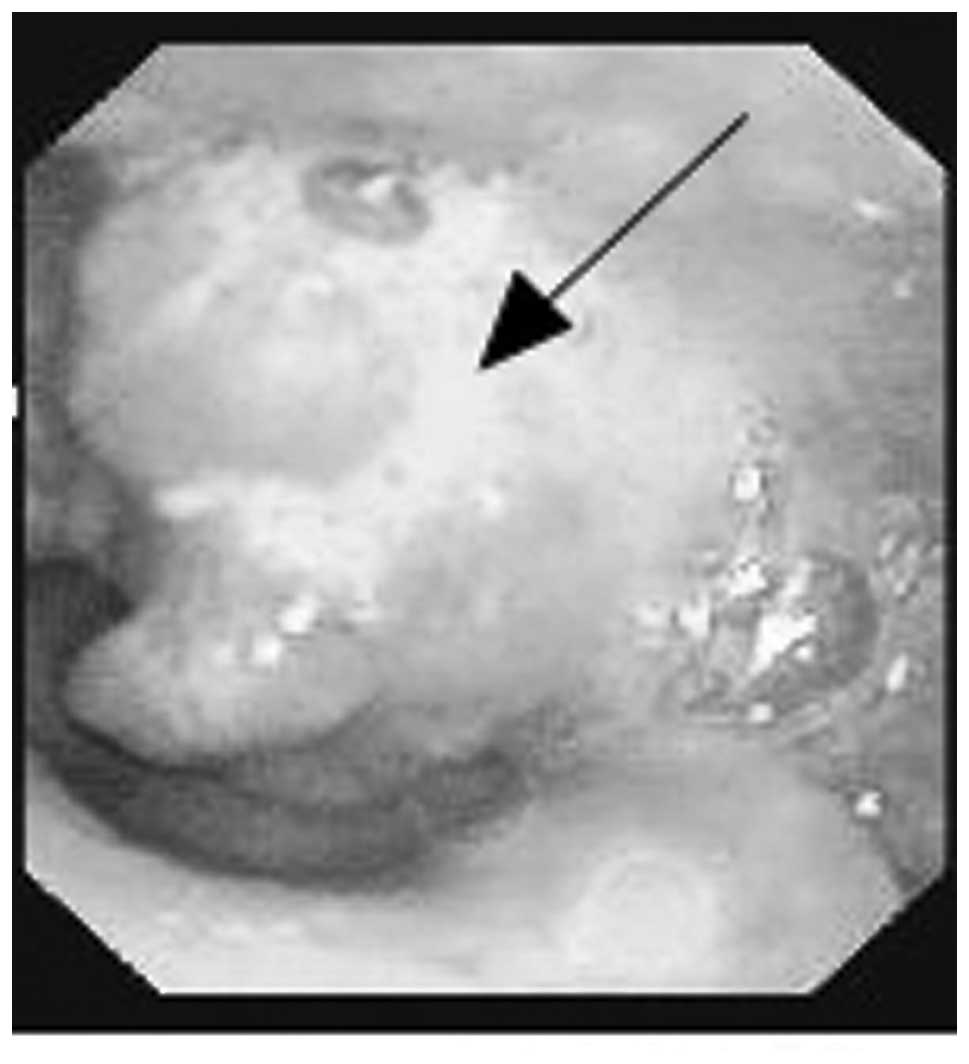

A 55-year-old male was admitted to the Department of Otolaryngology and Head and Neck Surgery, Sir Run Run Shaw Hospital, Medical College of Zhejiang University (Hangzhou, China) complaining of a mass on the left side of the neck, which had been present for six months. The patient reported that the mass had increased rapidly over the two preceding months. The patient stated there was no tenderness or paresthesia, however, the mass had been punctured and pus had been extracted at the Jiangshan Beilin Hospital (Jiangshan, China). An endoscopy revealed a 1.5-cm submucosal mass in the left pyriform sinus, which extended to the lateral wall (Fig. 1). The posterior pharyngeal wall, vocal cords, subglottic region and the base of the tongue appeared to be healthy. Computed tomographic (CT) examinations demonstrated a soft tissue mass in the left pyriform sinus and a 4.4×4.1-cm lesion, which was not well defined from the surrounding healthy soft tissue on the left side of the neck (Fig. 2).

A 62-year-old male was admitted to the Department of Otolaryngology and Head and Neck Surgery, Sir Run Run Shaw Hospital (Hangzhou, China), to evaluate the presence of persistent hoarseness (six-month duration). An endoscopy demonstrated a mass on the left vocal cord, which markedly extended to the anterior commissure (Fig. 3). CT showed a 1.5×1.0-cm mass on the left vocal cord, at high resolution (Fig. 4). A total laryngectomy with neck dissection was performed. The surgically-removed tumor of the left vocal cord appeared cauliflower-like and was 1.5×1.3 cm in size. Follow-up of the patient 6 months postoperatively revealed pulmonary metastases.